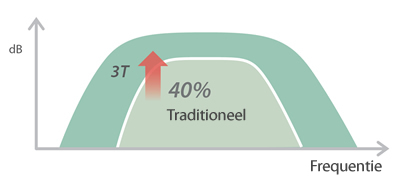

X-Insight adalah solusi untuk visualisasi lebih lanjut.

Dengan pemahaman mendalam atas kebutuhan pelanggan, DC-60 Exp dengan X-Insight dirancang untuk menyajikan efisiensi tinggi dengan pencitraan yang presisi, yang didukung oleh eXpress Clarity, eXceptional Intelligence, dan eXceeding Experience.